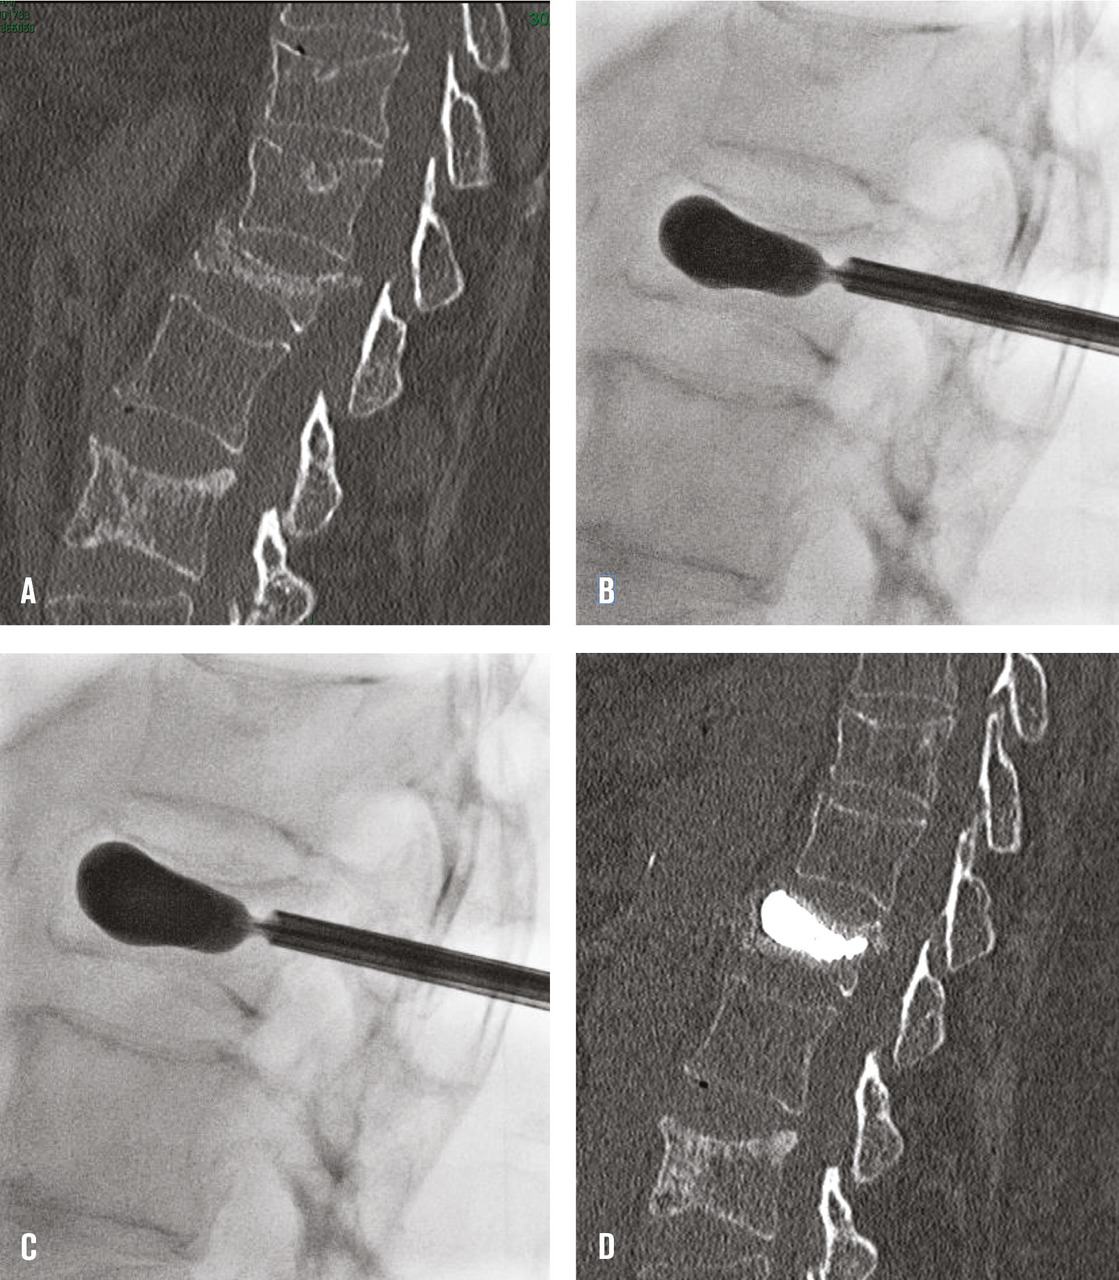

La vertèbre est abordée par voie postérieure, le plus souvent transpédiculaire, voie qui a l’intérêt de contenir dans la vertèbre un éventuel reflux de ciment. L’abord bipédiculaire demande plus de temps mais permet d’obtenir une meilleure répartition du ciment dans la vertèbre. Une fois le trocart en place dans le corps vertébral, 3 à 8 cc de polyméthylméthacrylate, selon la taille de la vertèbre, sont lentement injectés sous contrôle scopique afin de s’assurer de l’absence de fuite extravertébrale (fig. 1). Il faut s’efforcer d’obtenir un remplissage du corps vertébral allant d’un plateau vertébral à l’autre pour former un étai et prévenir le risque de nouvelle fracture du même corps vertébral.

Dans la cyphoplastie, des ballonnets sont mis en place par voie transpédiculaire dans le corps vertébral fracturé, puis gonflés sous pression pour relever le plateau vertébral enfoncé et créer ainsi une cavité intracorporéale (fig. 2). Les ballonnets sont ensuite dégonflés et retirés et le ciment injecté à basse pression afin de remplir la cavité créée, ce qui diminue le risque de fuite extravertébrale de ciment. À côté de la cyphoplastie à ballonnets sont maintenant proposés de nombreux dispositifs de réexpansion vertébrale tels que des stents ou des « cricks » qui servent à repousser le plateau vertébral enfoncé mais sont laissés en place et « coulés » dans le ciment. Ils sont plus utilisés dans les fractures traumatiques ou malignes que dans l’ostéoporose. L’objectif de la cyphoplastie à ballonnets et de ces dispositifs est de réduire au moins partiellement l’angle de cyphose vertébrale qui est parfois important dans certaines fractures cunéiformes.